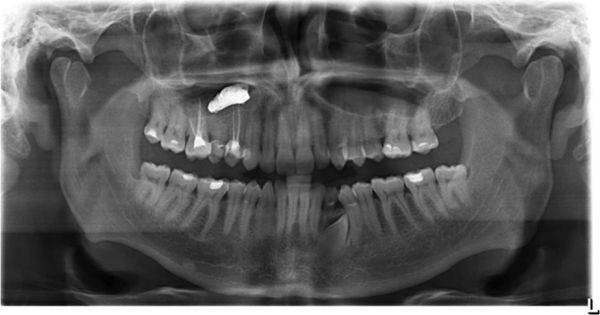

В основном мицетома гайморовой пазухи образуется тогда, когда через сообщающийся канал зуба в неё попадает пломбировочный материал. В состав пломбы входят оксид цинка и сульфат бария, образующие пищевую среду для аспергиллов, что провоцирует развитие мицетомы.

![Пломбировочный материал в гайморовой пазухе [15]](/pimg3/luchevaya-diagnostika-mukotsele-8E9F8AA.jpeg)

Мультиспиральная компьютерная томография остаётся эффективным и единственным способом диагностики мицетомы околоносовой пазухи. Использование трёхмерной реконструкции даёт представление об объёмном взаиморасположении костей, позволяет оценить состояние верхнечелюстной пазухи и зубочелюстной системы (целостность зубов, степень разрушения, цвет, положение в зубном ряду, подвижность, глубину зубодесневых каналов), а при наличии инородных тел точно показывает их форму, размер и местонахождение.